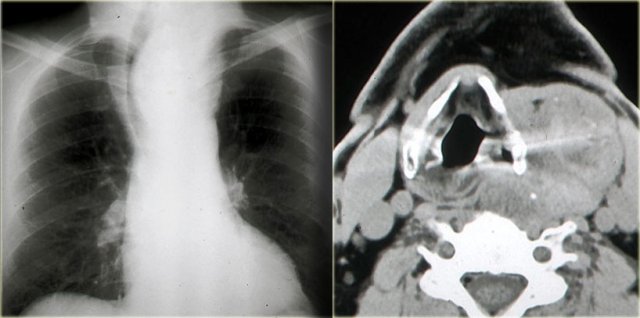

Lemierre' s syndrome

When you diagnose an acute thrombosis of the internal jugular vein, always look for pulmonary symptoms, i.e. Lemierre' s syndrome.

The oral infection spreads into the neck and causes internal jugular vein thrombophlebitis with subsequent septic emboli.